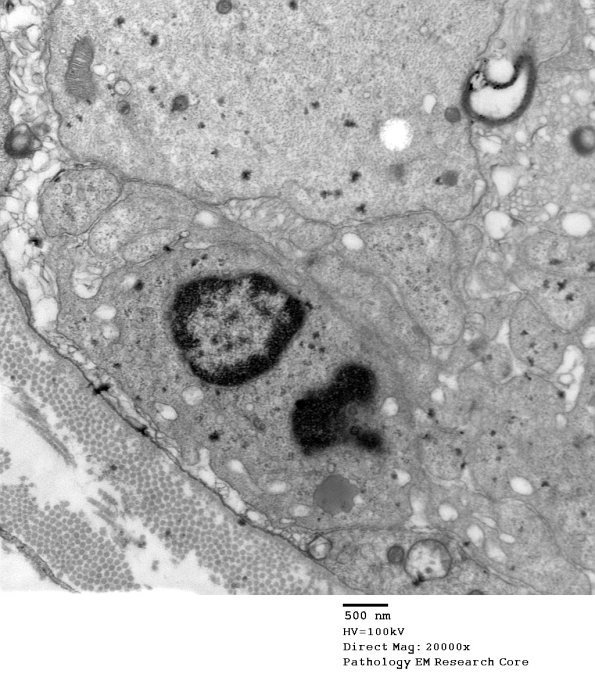

Multiple cells have entered the sub-basal lamina space and engulfed myelin debris, a process largely completed. (electron micrographs)